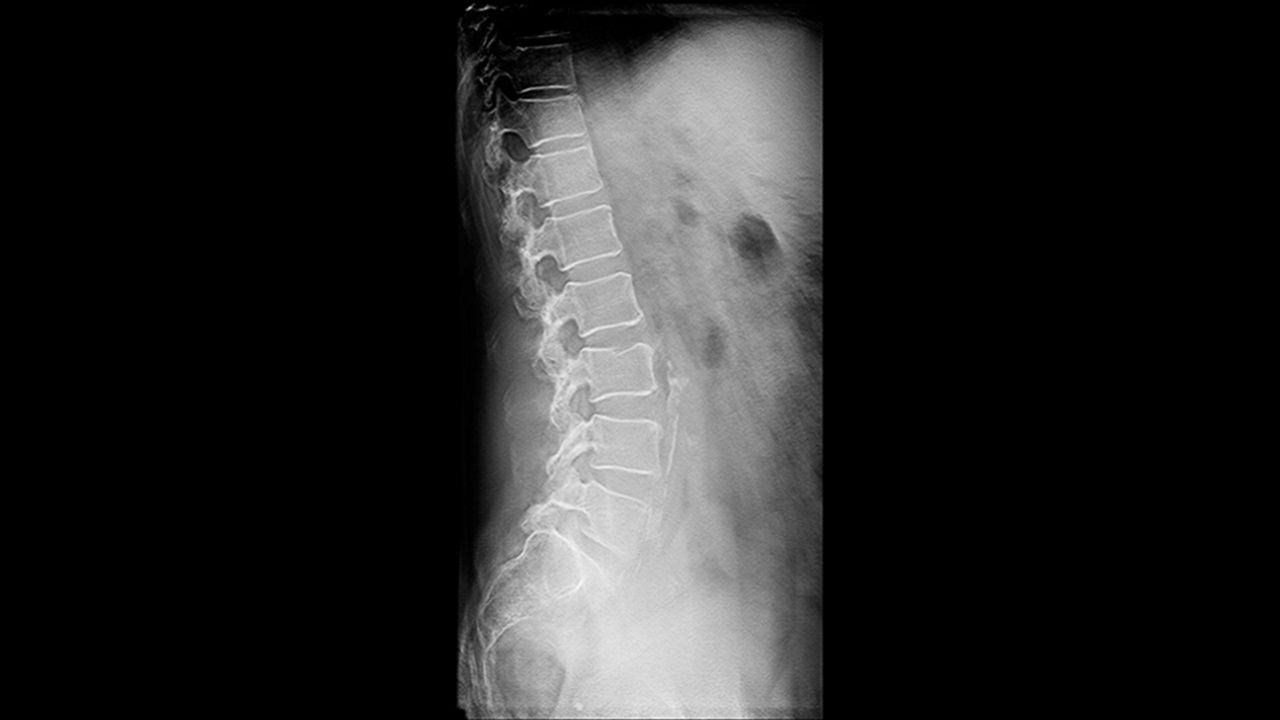

VolumeRAD™ digital tomosynthesis

Improves clinical diagnosis by removing overlaying structures and enhancing local tissue separation.